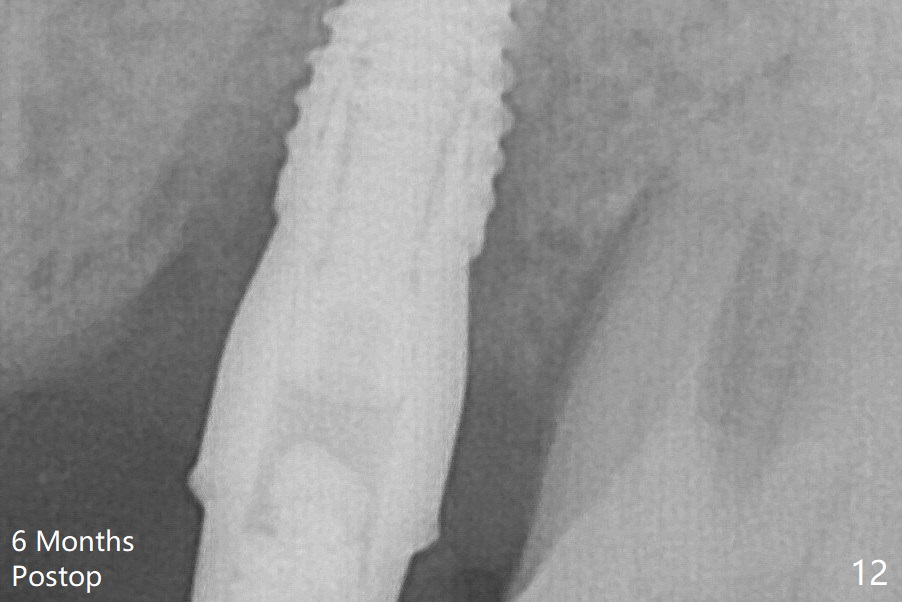

Bone density between #13 and 14 appears to increase 3 months postop (Fig.10). There seems to be more bone growth (i.e., decreasing gap) 6 months postop (Fig.12).